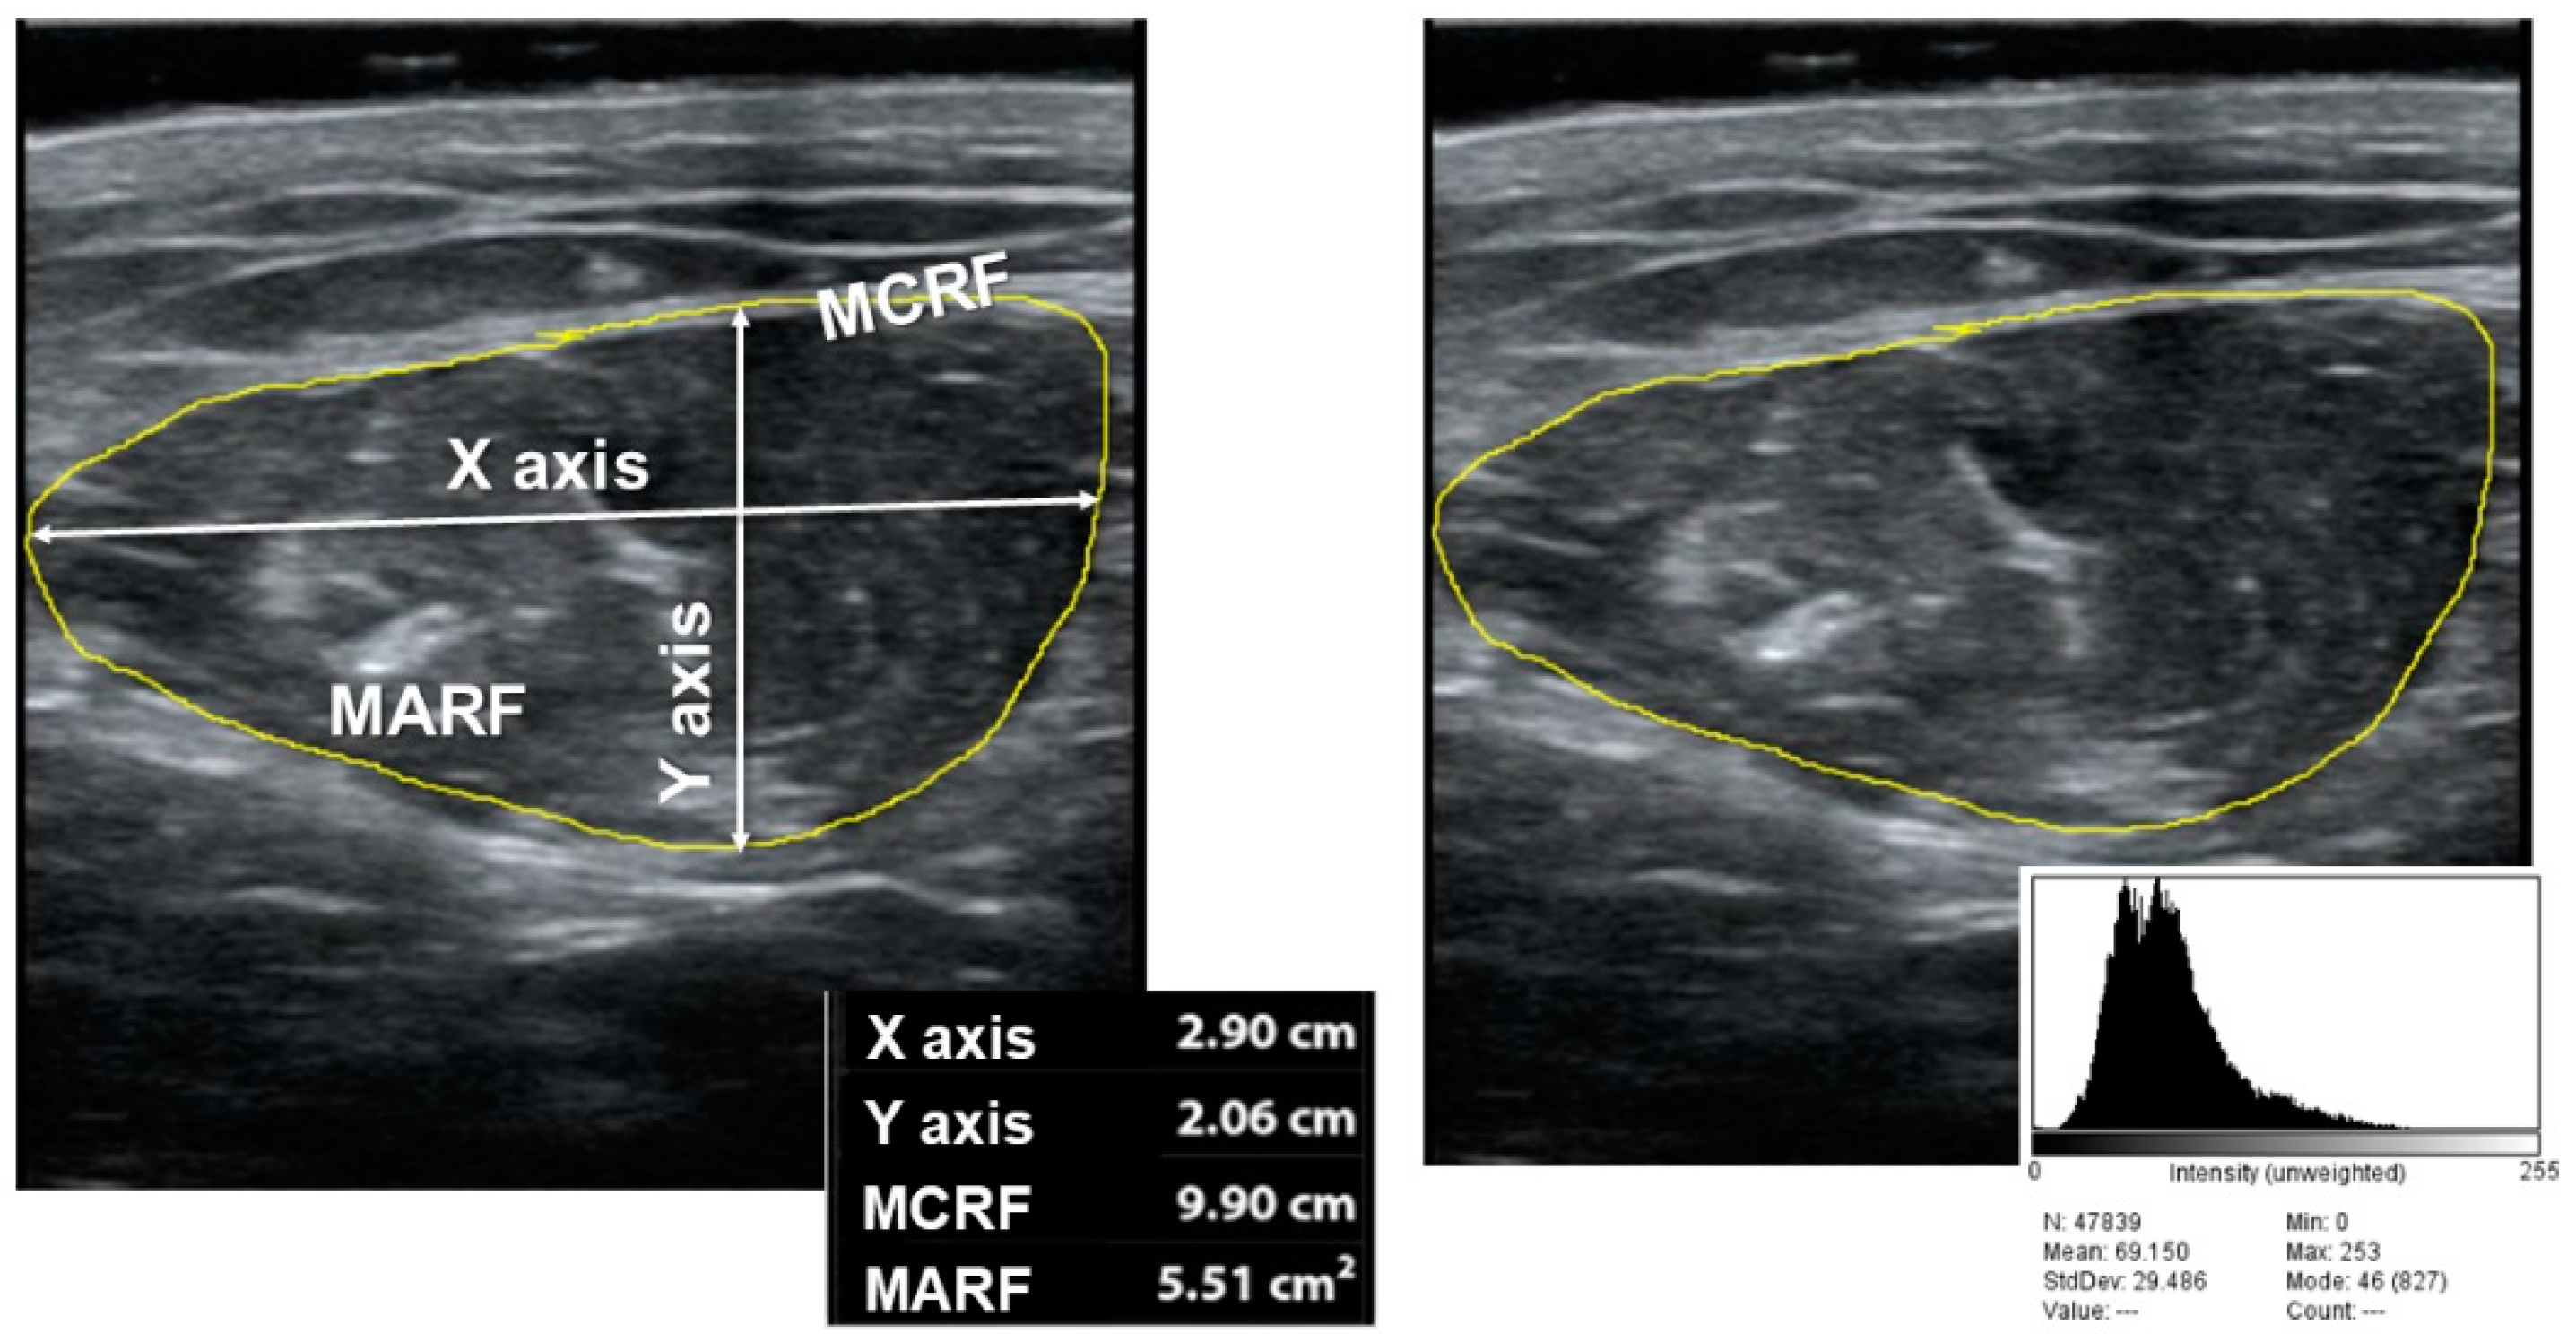

- Nutritional Ultrasonography: We made a muscular ultrasonography of the quadriceps rectus femoris (QRF) of the dominant lower extremity with a 10 to 12 MHz probe and a multifrequency linear matrix (Mindray Z60, Madrid, Spain). The measurement was made with the patient in the supine position. The probe was aligned perpendicular to the longitudinal and transverse axis of QRF. The determination was performed without compression at the level of the lower third from the superior pole of the patella and the anterior superior iliac spine [14].